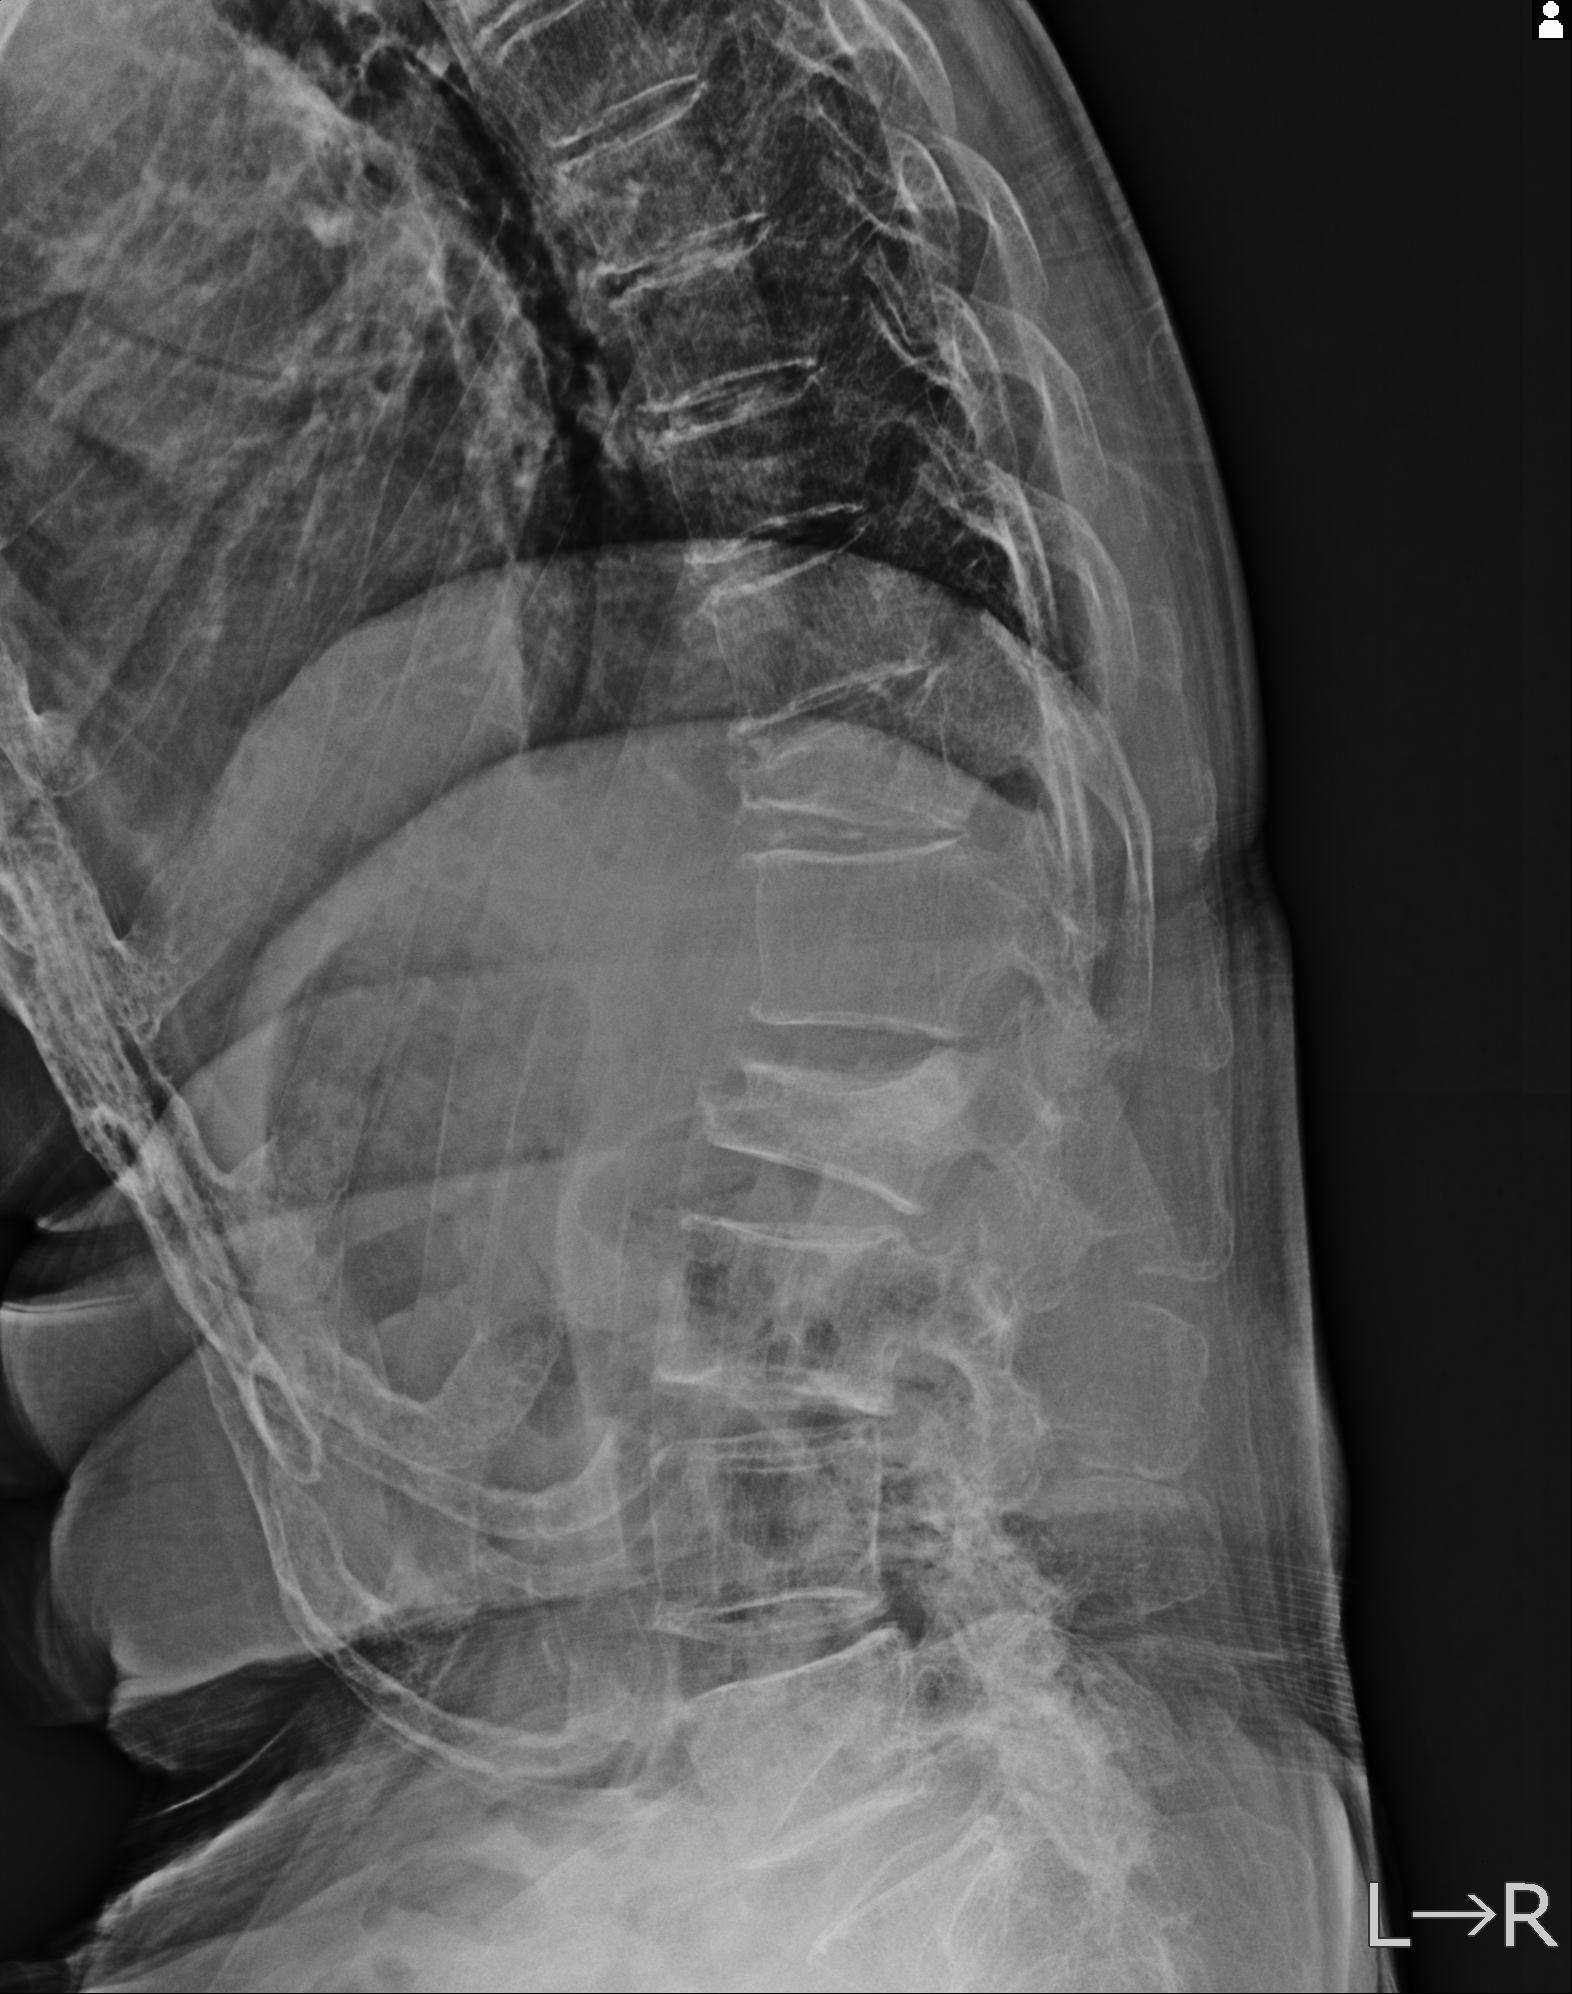

102916 2/1 と 3/22 腰椎 2R 74歳女性 LIFX

93804 2/9 腰椎 2R 後方固定 67歳女性